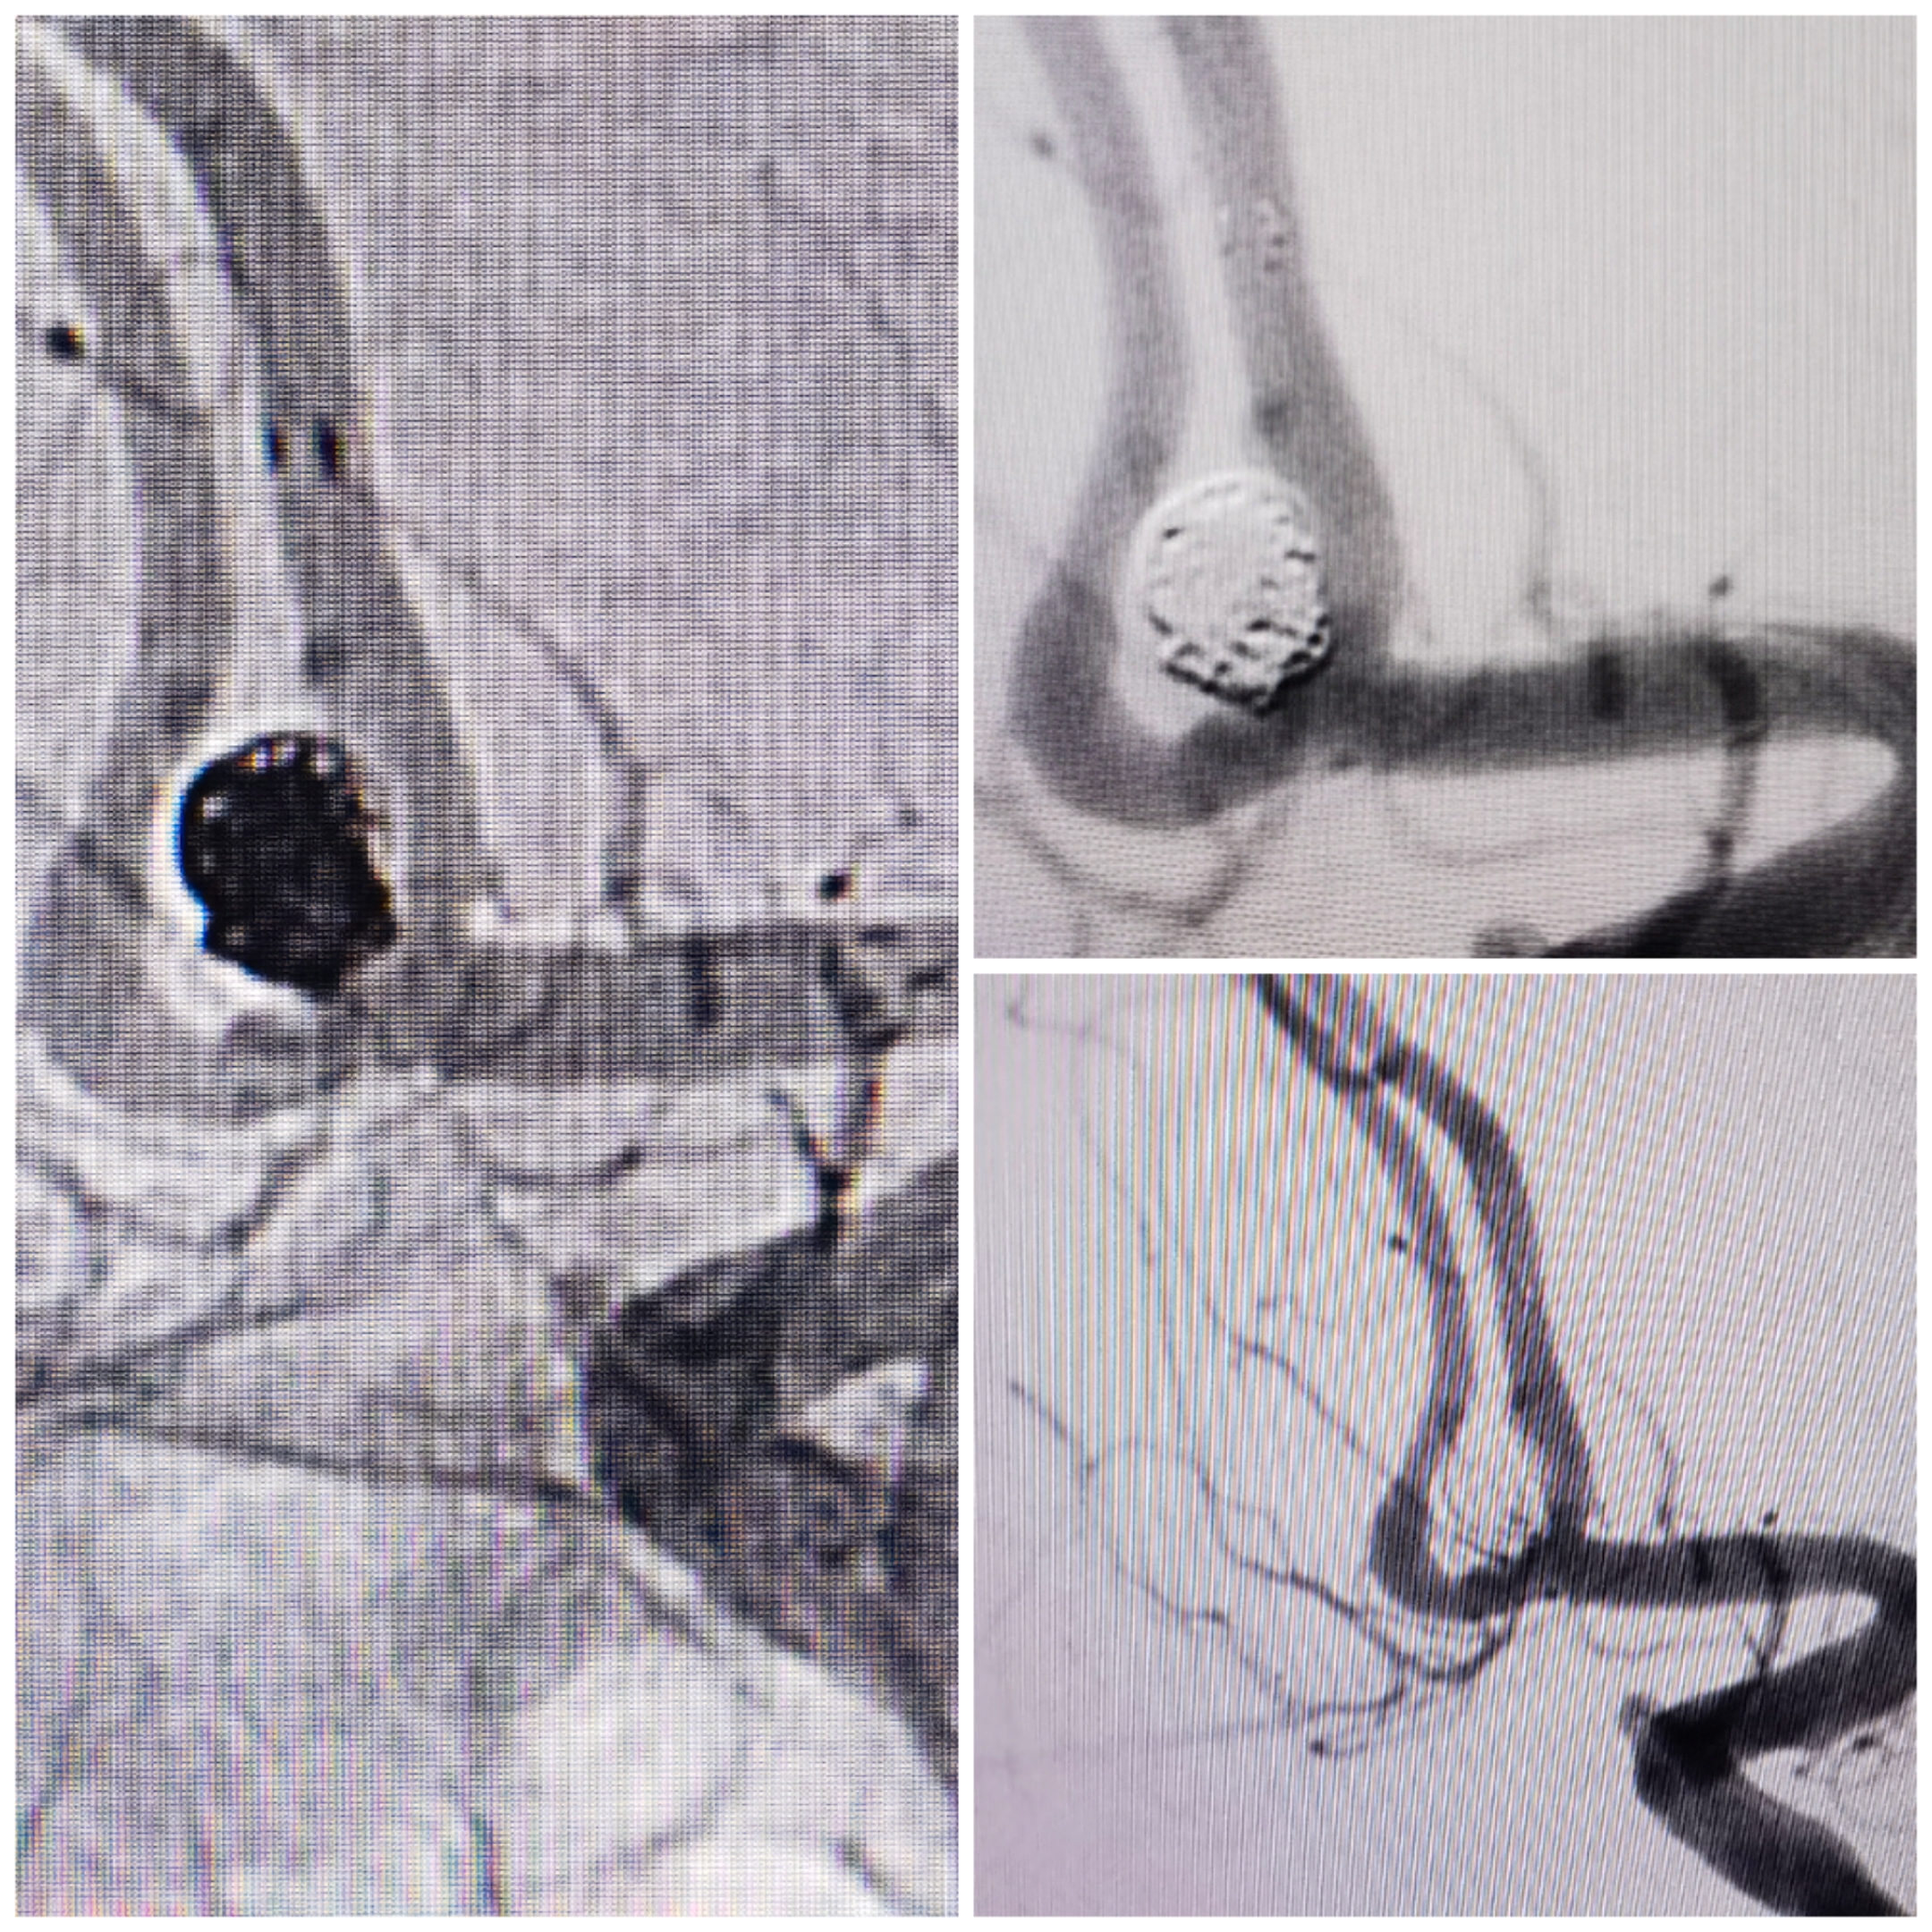

术后栓塞情况:支架开放良好,弹簧圈致密栓塞,双侧大脑前血流良好

术后3D重建情况

术后支架CT重建